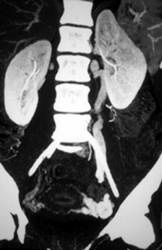

Early Pregnancy